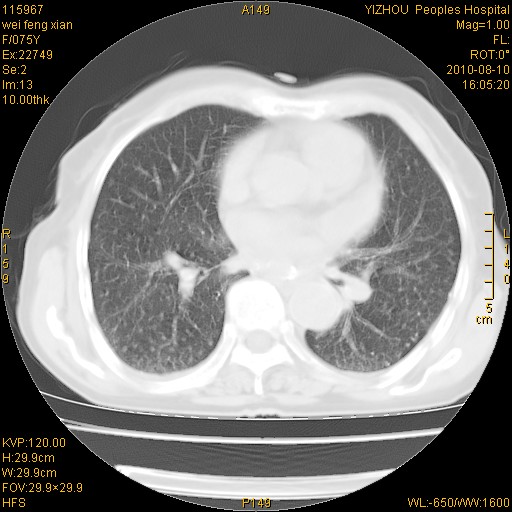

标题: CT28313:两肺弥漫性病变

女,75岁,患者反复头昏乏力面色苍白3年,再发10天入院。临床贫血查因。

双肺间质增生并右肺上叶炎性改变,不除外右肺上叶结核病肺内播散

考虑右肺上叶炎症合并双肺结核可能性大,建议上传纵隔窗ct图片。

双肺结核可能性大

考虑尘肺并结核;右上肺支气管扩张!

结核、尘肺、支气管肺泡癌都不能除外

右肺上叶继发性肺结核伴肺内血型播散!

考虑右肺上叶继发性肺结核伴两肺播散。